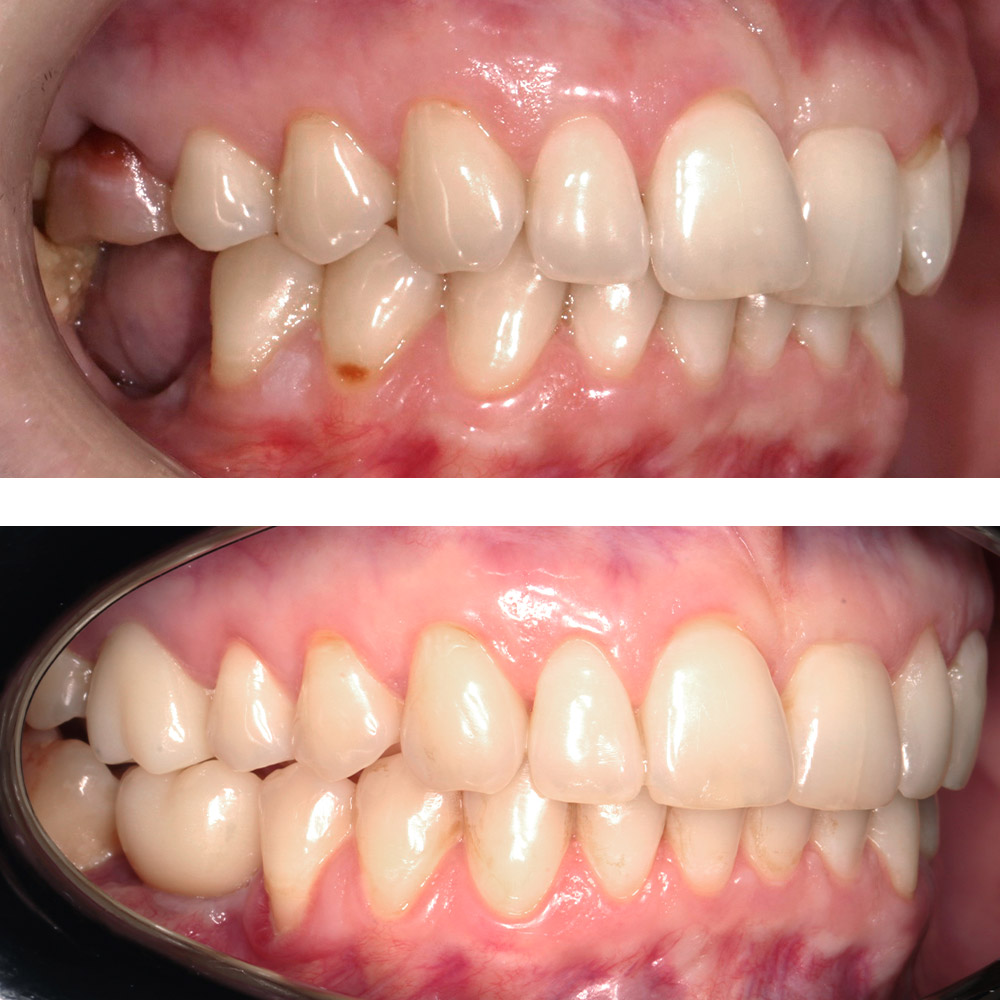

Кейс 21

Юрченко Павел Николаевич

Количество кап ВЧ 32

Количество кап НЧ 32

ДО

ПОСЛЕ